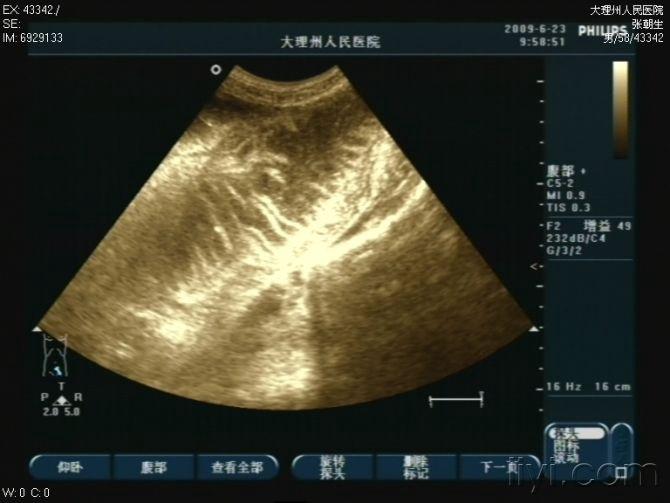

阑尾炎术后肠梗阻一例

图片尺寸720x576